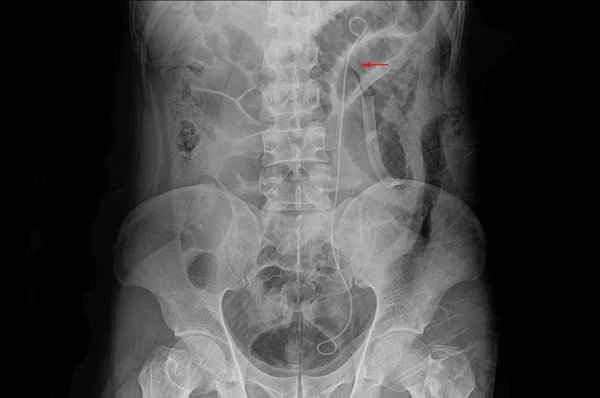

Intestinal polyps are growths that appear on the inner wall of the intestine, usually caused by abnormal proliferation of intestinal wall cells. These polyps are typically located in the large intestine, including the colon and rectum. Their growth is localized and does not penetrate the intestinal wall outwards. The presence of polyps can lead to problems such as intestinal obstruction or bleeding, so timely diagnosis and treatment are crucial.

When dealing with intestinal polyps, it's important to understand the meaning of the test results and follow your doctor's advice for further examination or treatment. Colonoscopy is a common method for diagnosing intestinal polyps, allowing direct observation of their size, shape, and location. The numbers on the test results usually indicate the number and size of the polyps, but this does not directly determine whether they will become cancerous. It's crucial to interpret the test results objectively and be alert to potential complications or side effects during treatment.